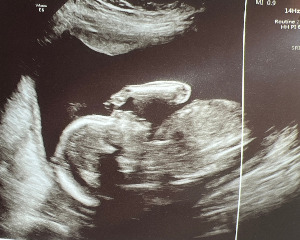

금이 초음파 사진 2.jpg

너의부모 자랑삼아 초음파픽 보내줬네

사진본들 무얼알까 영상봐도 모를텐데

생애처음 인사하네 사진속의 태아에게